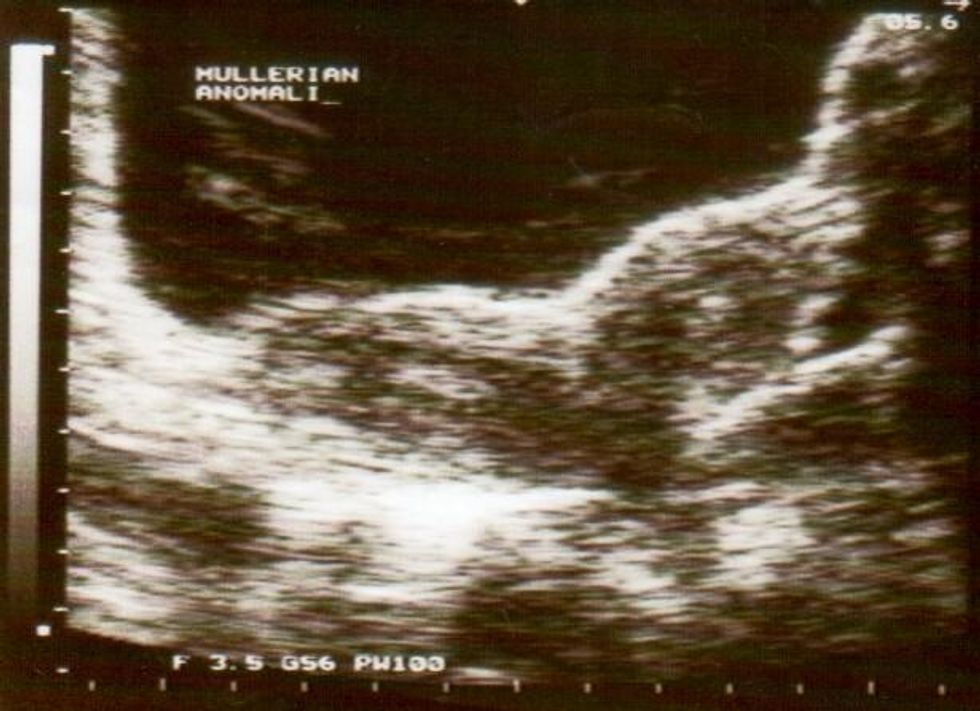

She had been born with two uteruses, two cervixes, and two vaginas.

Claire was diagnosed with uterus didelphys, a rare condition leads to the development of extra organs.

Didelphys

According to the World Health Organisation, around 3000 women suffer from uterus didelphys.

In a female fetus, the uterus starts out as two small tubes. As the fetus develops, the tubes normally join to create one larger, hollow organ — the uterus.

Sometimes, however, the tubes don't join completely. Instead, each one develops into a separate structure.

Doctors claimed they were unaware of Wright's condition, because the septum between the two cervixes was so thick, the second was obscured.